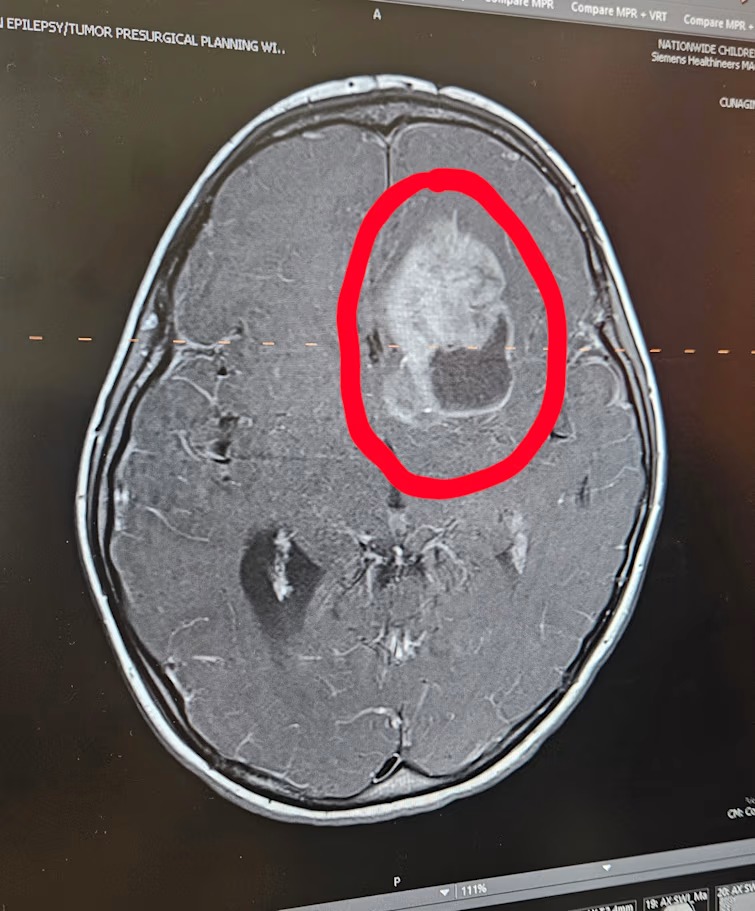

Ashton had a seizure with no history of seizures. We went to Grove City Methodist Hospital, who discovered a mass in his brain. They quickly transferred us to Nationwide Children's Hospital (NCH). While in the emergency department, Ashton had another seizure. We were sent to the PICU and had MRIs and other testing completed. He underwent surgery on July 1st, and by God’s grace, they were able to do a full removal of the tumor. Since then, he has been home recovering from surgery and acting like his normal self. He has been healing at a remarkable rate, and we are thrilled to see his progress! Ashton had a follow-up MRI as well as a Lumbar Puncture last week, and the MRI showed no sign of any growth or concerns for tumor growth, along with the LP coming back negative for malignancy.

After the biopsy and molecular testing, it was determined to be CNS neuroblastoma with FOX-R2 alteration. It's a newer diagnosis category and fairly rare. This is an embryonal tumor, though that really only matters for the oncology team for the exact treatment plan. The good news is that research has changed in the last couple of years, and treatment can have very good results. As high as 85% chance that after treatment, Ashton will stay disease-free for 3 years. This was the best possible result, and we feel so blessed that this is our path.